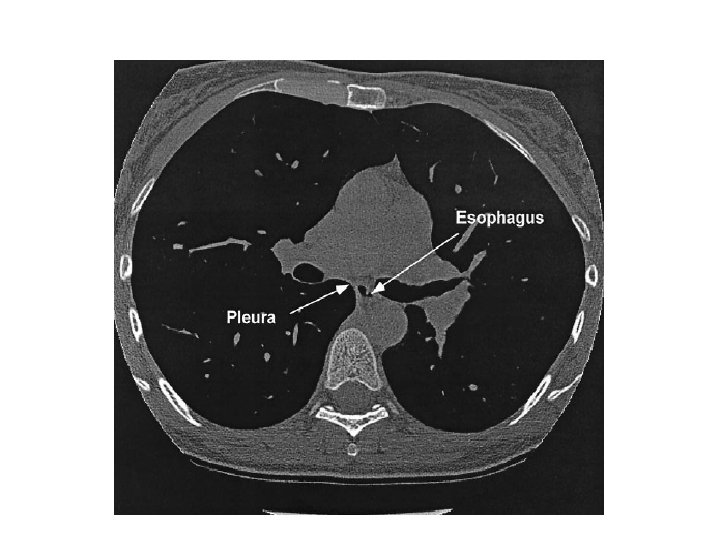

Measurement Indirect measurement. Esophageal pressure. Lower one third of the esophagus. Upright posture. Analysis of lung and chest wall compliance, work of breathing, respiratory muscle function and the presence of diaphragm paralysis. • Mechanical ventilation guided by esophageal pressures in ALI. November 13, 2008. • •